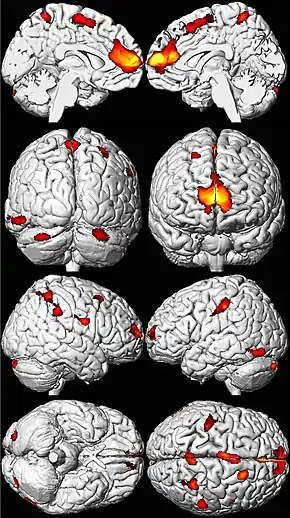

Les zones de perte de volume cérébral apparaissent ici en couleur sur un modèle de cerveau normal[197].

Une première étude a suivi, de 1979 à 1984, la plombémie d'un panel de bébés exposés au plomb à Cincinnati. Environ 20 ans plus tard, quand ils ont eu de 19 à 24 ans, leur volume cérébral a été mesuré par IRM ; l'exposition au plomb durant l'enfance était liée à une perte de volume cérébral à l'âge adulte, surtout chez les hommes et avec un effet "dose-réponse". La perte de matière cérébrale était plus marquée dans le cortex préfrontal et notamment dans le « cortex cingulaire antérieur »[199]. Une corrélation a été observée entre le volume cérébral et les mesures du fonctionnement cérébral, et avec le contrôle de la motricité fine (mais pas avec les autres mesures). Selon les auteurs, l'effet plus net chez les hommes pourrait peut être expliquer que les comportements antisociaux soient chez eux plus fréquent que chez les femmes. Ils plaident pour des efforts accrus de protection des enfants contre l'exposition au plomb[199].